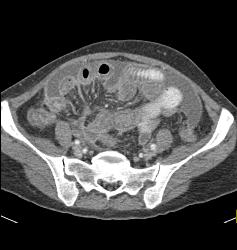

Linitis Plastica With Carcinomatosis